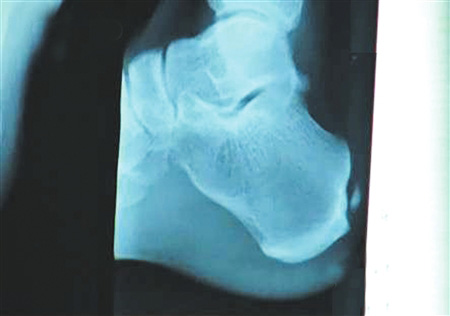

手術(shù)要取出的鈣化物就在這里。 圖片來源:華西都市報(bào)